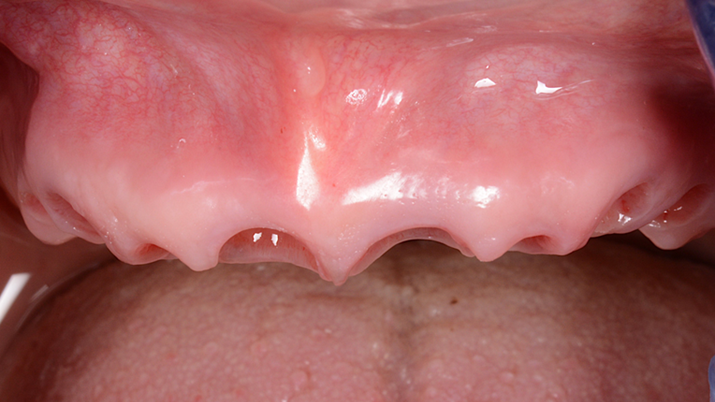

Clinical case: A Full transition from natural teeth to all-on-6 bridges

with AnyRidge implants

- Courtesy of Dr. Rabih Abi Nader, UAE -